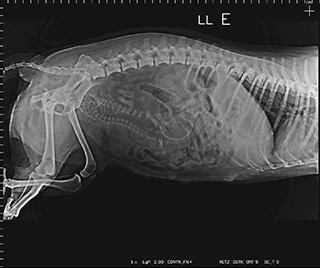

Radiologia Digital Direta / Digital Radiography

As radiografias geradas digitalmente podem ser transmitidas para iPad Apple®, notebooks e smartphones.

iPad com tela Retina Apple® possibilita a visualização das imagens com maior qualidade diagnóstica.

Envio Digital Automático (EDA) permite a distribuição das radiografias sem necessidade de impressão.

O responsável pelo paciente pode receber as radiografias em seu smartphone ou computador.

Radiologistas podem receber as imagens por e-mail para laudo, de forma prática. 100% DIGITAL

OMNYRADTM DR tem a operação mais simples entre todos os equipamentos oferecidos no mercado.